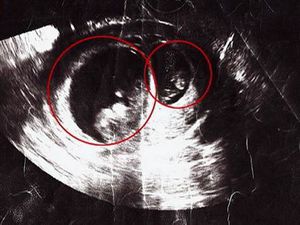

Superfetation is when a pregnant woman becomes pregnant again. It is characterized by the fertilization and the implantation of a second fertilized egg in a uterus already containing a fetus or zygote. With superfetation, the two fetuses have different due dates. Superfetation can occur in some animals but is so rare in humans that fewer than 10 cases have been reported in the medical literature